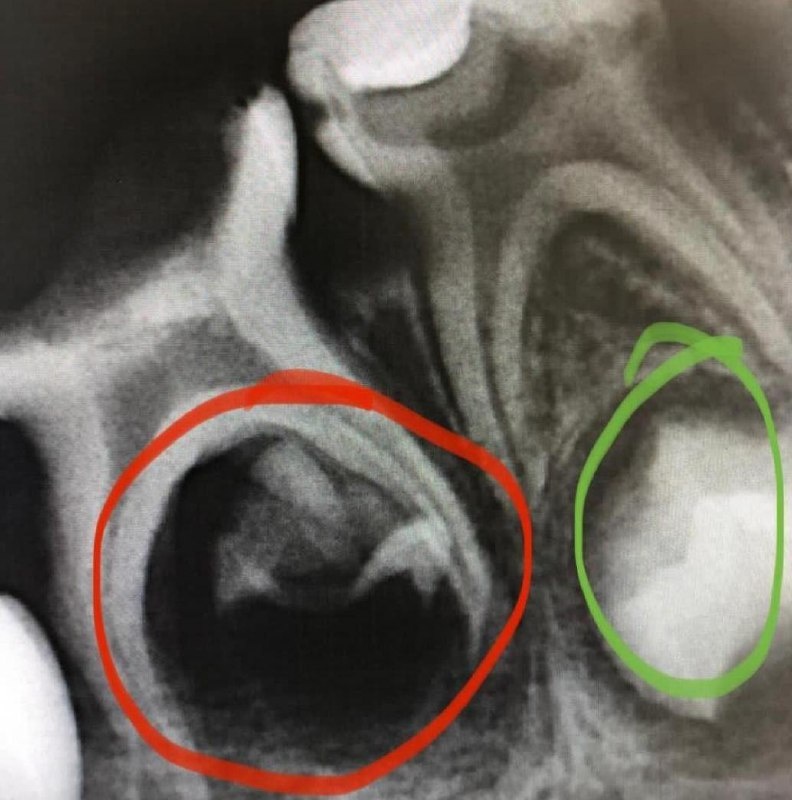

Пример: На снимке два молочных зуба, под которыми находятся зачатки постоянных зубов — зеленый кружочек. То, что отмечено красным — погибший зачаток, инфекция на который попала с молочного зуба. Родители этот зуб решили не лечить, мол, сам выпадет через пару лет - частая ошибка. Итог — у ребенка никогда не вырастет постоянный зуб на этом месте.